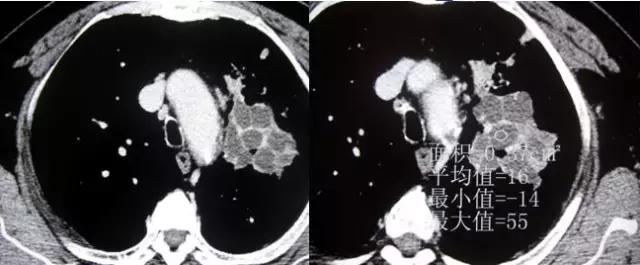

附:支气管粘液嵌塞

粘液支气管征或支气管粘液嵌塞:是由于扩张的支气管腔内分泌粘液无法排出或近端梗阻而郁积等原因所致。

CT表现:表现为分支状或指状致密影,呈指套征或“V”、 “Y”形征。

意义:表明有支气管扩张分泌粘液,支气管近端有梗阻粘液不能排出而郁积以及支气管闭索等。

分析斟酌:扩张的支气管充满粘液呈纵行束状排列